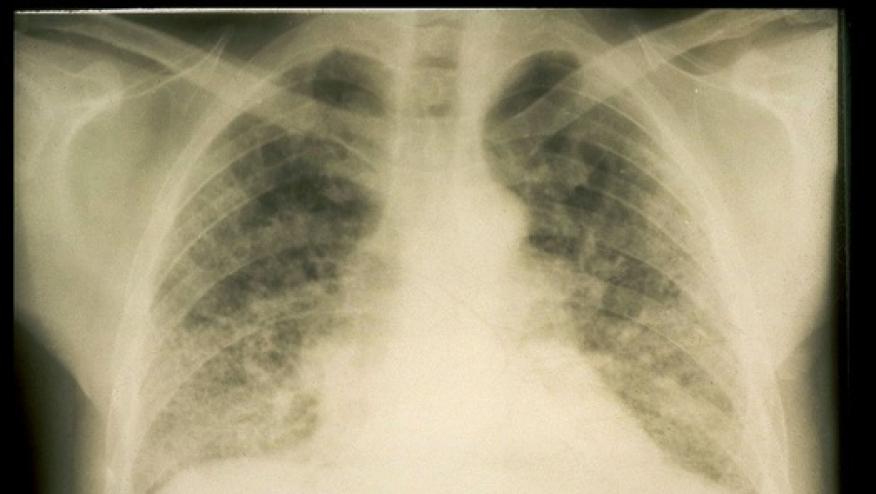

The diagnosis of chronic lung disease in patients with systemic sclerosis may be difficult because of atypical symptoms, variable evolution and limitations of current classification criteria for a definite diagnosis. Nevertheless, diagnosis is necessary as patients with SSc-ILD have a poorer prognosis than those with SSc without pulmonary involvement. Vrancken and colleagues present a case report and brief review of this challenging complication.